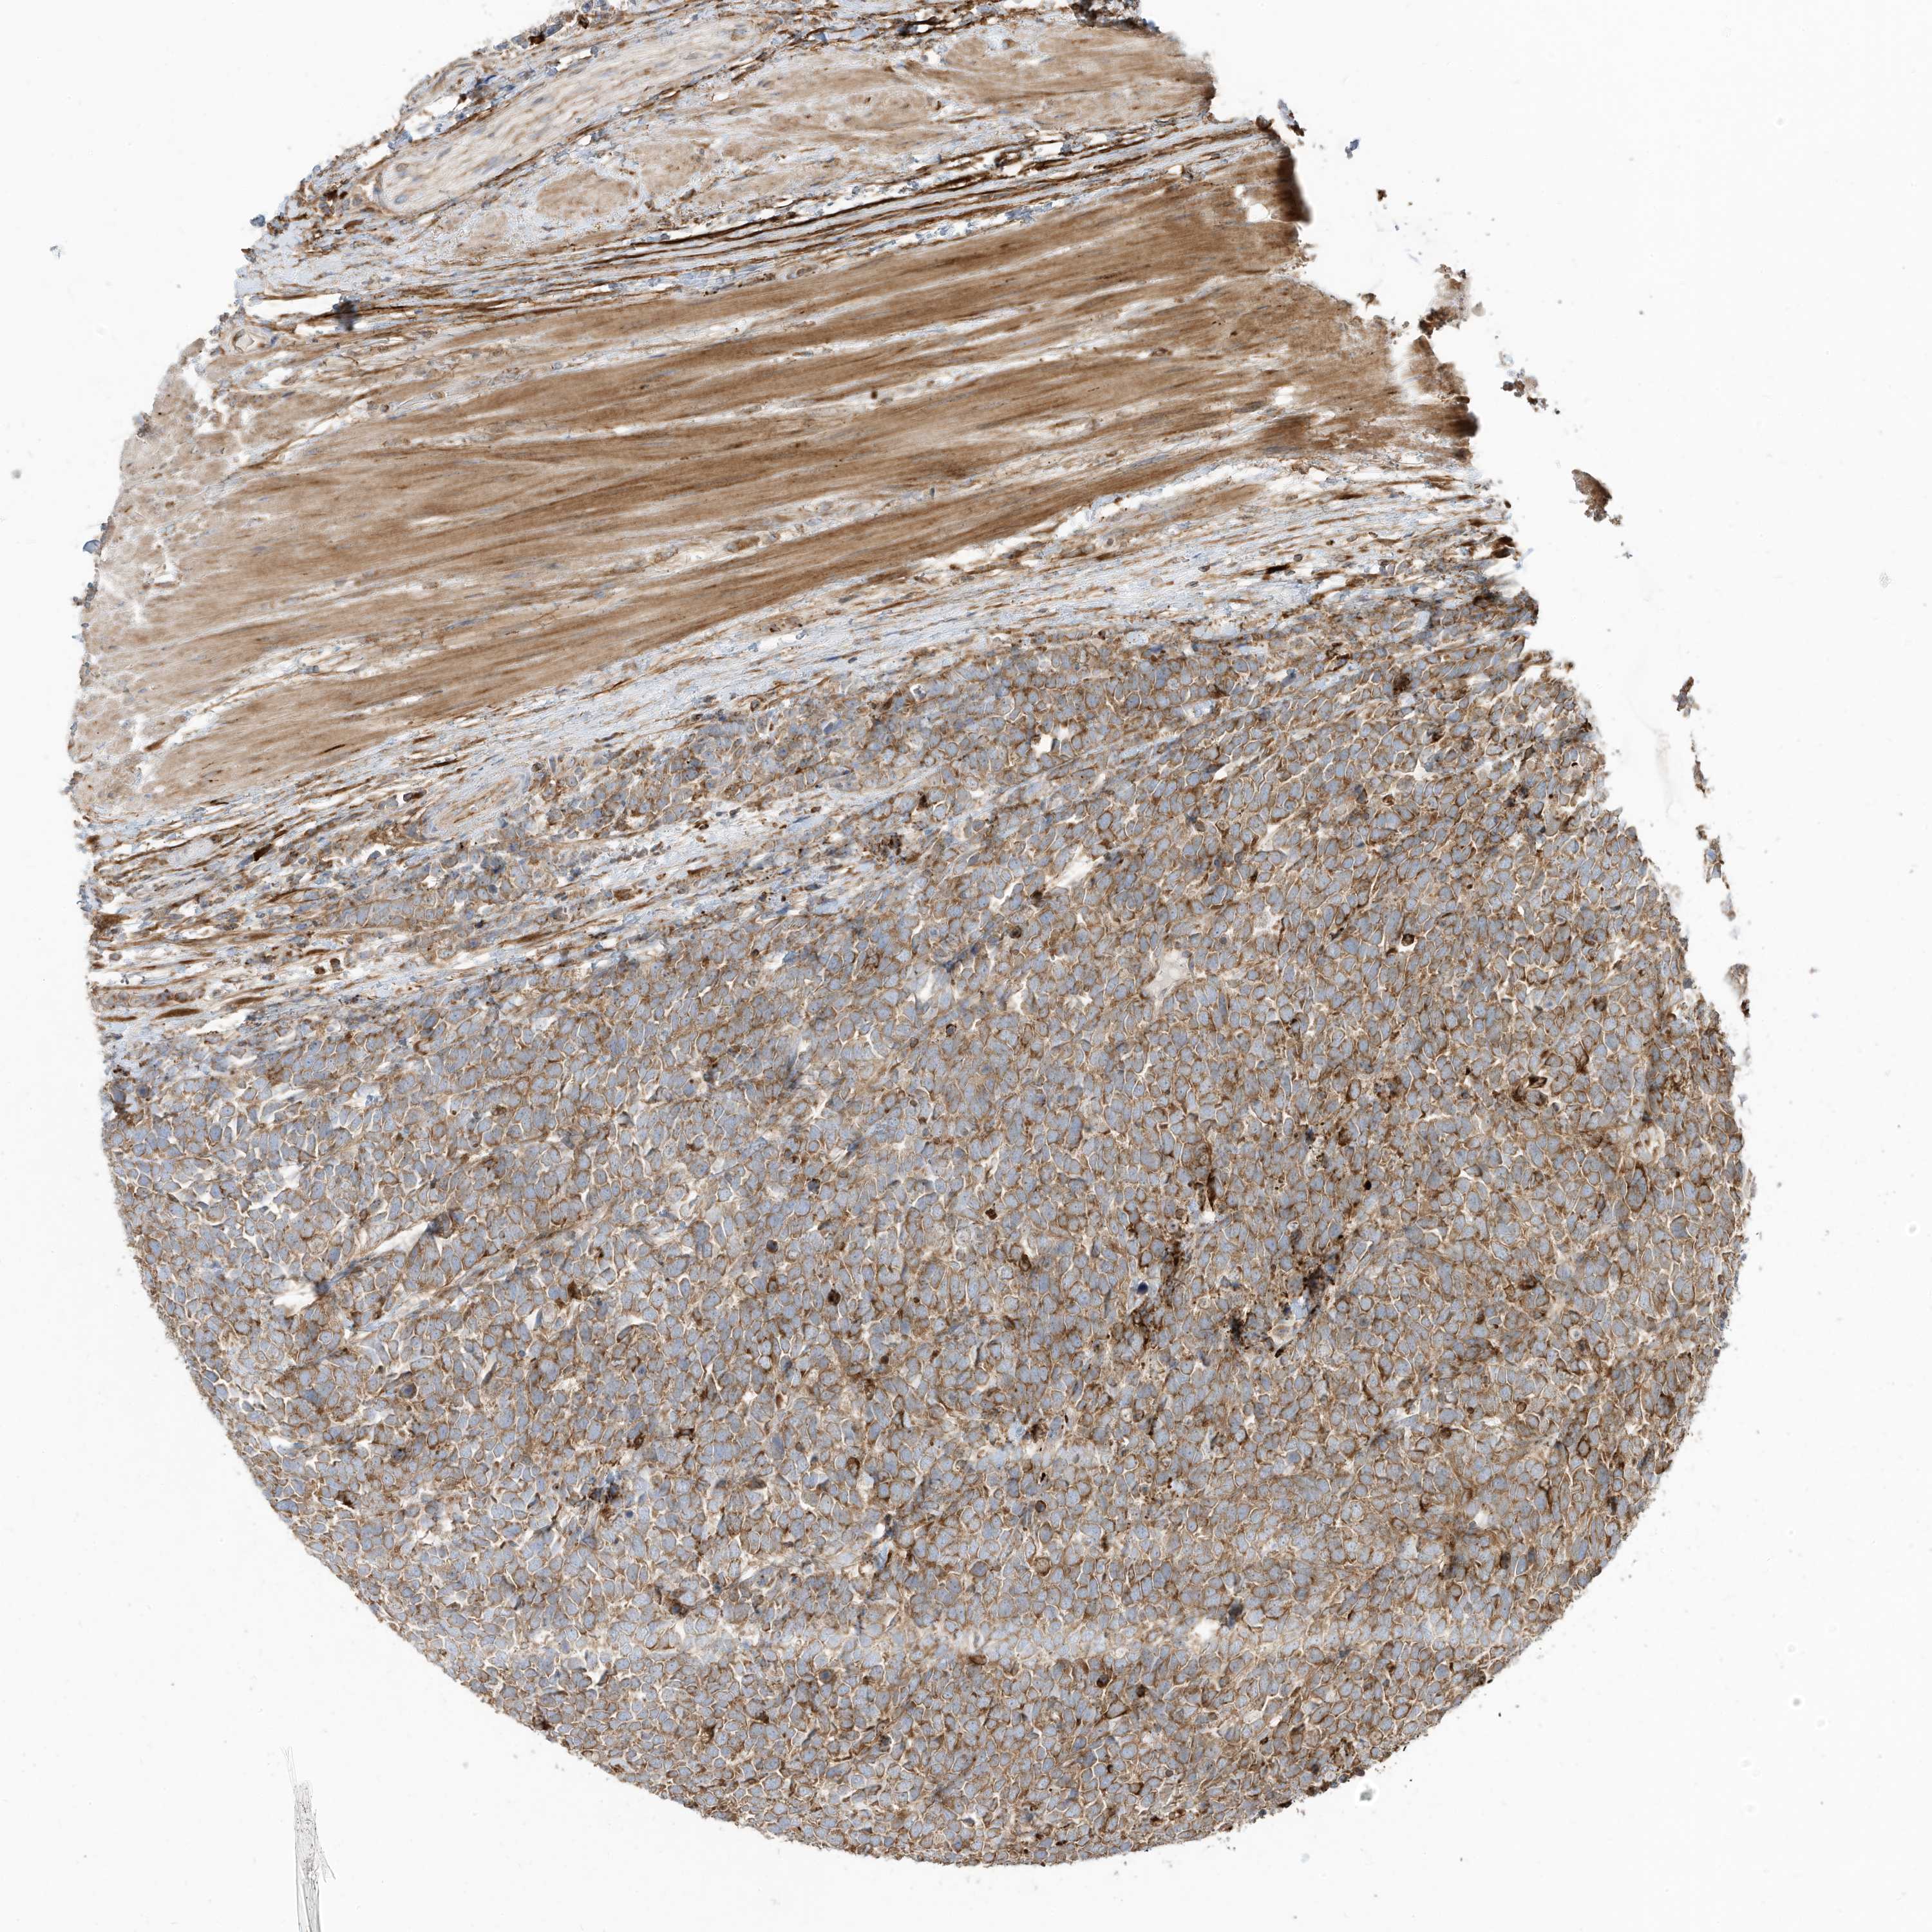

UROTHELIAL CANCER - Protein expressioni

A mouse-over function shows sample information and annotation data. Click on an image to view it in a full screen mode. Samples can be filtered based on level of antibody staining by selecting one or several of the following categories: high, medium, low and not detected. The assay and annotation is described here.

Antibody stainingi

Antibody staining in the annotated cell types in the current human tissue is reported as not detected, low, medium, or high, based on conventional immunohistochemistry profiling in selected tissues. This score is based on the combination of the staining intensity and fraction of stained cells.

Each image is clickable and will lead to virtual microscopy that enables deeper exploration of all samples and also displays staining intensity scores, fraction scores and subcellular localization as well as patient and tissue information for each sample.

Antibody HPA032069

Staining

High

Medium

Low

Not detected

Intensity

Strong

Moderate

Weak

Negative

Quantity

>75%

75%-25%

<25%

None

Location

Nuclear

Cytoplasmic/membranous

Cytoplasmic/membranous,nuclear

Urothelial carcinoma, Low grade

Urothelial carcinoma, High grade